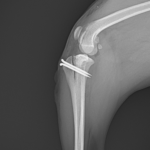

膝蓋骨内方脱臼G3

ポメさんがソファーからジャンプした後から急性の跛行を呈しているとのこと。もともと存在していた膝蓋骨内方脱臼が憎悪した可能性があります。ブロックリセッション大腿骨滑車深化術、脛骨粗面外側移行術、関節包の縫縮で対応しました。しばらく安静が必要です。